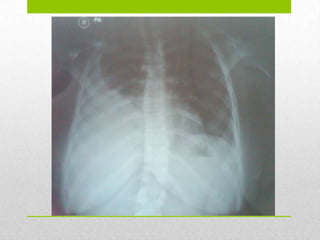

Técnicas de Imagen

 Radiografía de tórax

 75% de los casos

 Presencia de masa tumoral o signos indirectos

 Radiografía PA de tórax: Lesión radio opaca que ocupaba parte de

la base de pulmón derecho